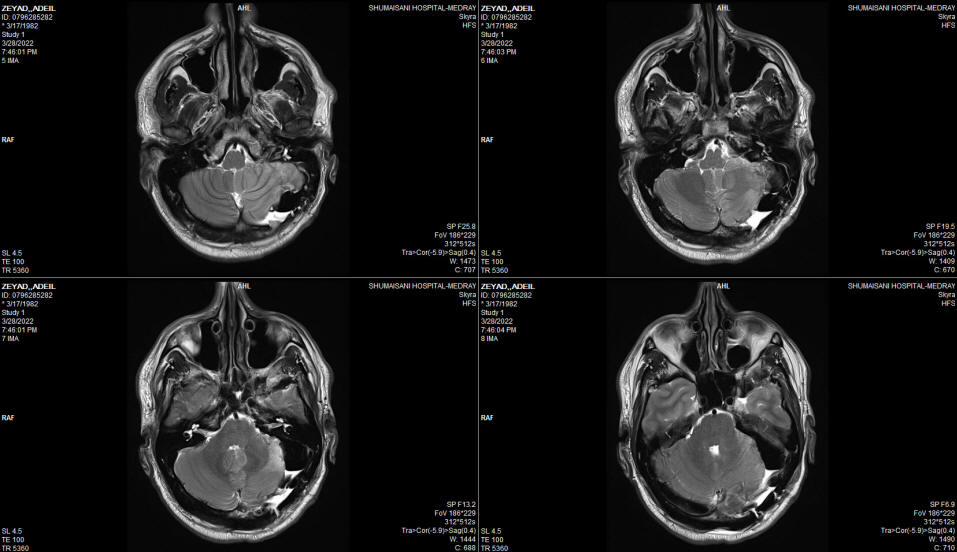

The patient came to the clinic 20-July-2016 complaining of left trigeminal neuralgia for 1 year. MRI done 21-September-2015 and 24-January-2016 showing a possible loop of the SCA compressing the left trigeminal nerve. There was suspicion of meningioma with hyperostosis which was denied. The patient is neurologically free and all medications failed to improve his condition, instead causing sleepiness and drowsiness.

The patient then came 26-June-2002 complaining of double vision, complete hearing loss left side, but he walk without aid with almost complete recover of the left facial nerve. Still complaining of swallowing difficulty, but he mention that the assort of the eating food is widening, but still using PEG.  MRI of the brain done 06-July-2022 showing massive malacia of the left cerebellar hemisphere. The brain stem and the posterior circulation are intact. The MRV showing absent left transverse sinus , which could be a variant. The left trigeminal nerve is not compressed and the canal is wide.

Fig:-3 Severe malacia and atrophy of the left cerebellar hemisphere with preserved brainstem.